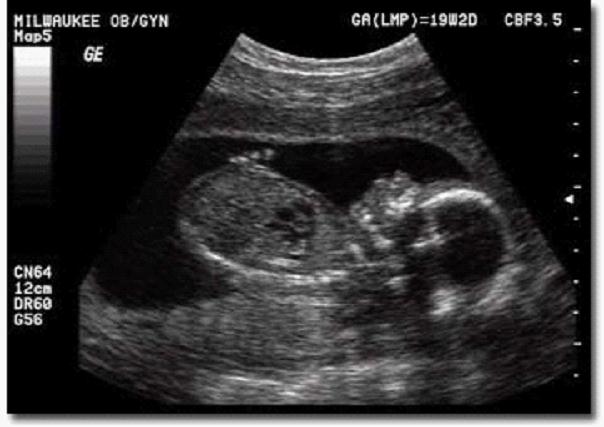

胎儿超声心动图,又称胎儿心脏超声扫描,是指利用医用超声波扫描设备,经孕妇腹部,系统检查胎儿心脏及大血管结构、节律和功能的临床诊断技术。

胎儿超声心动图检查的合适时间?

孕20-30周之间